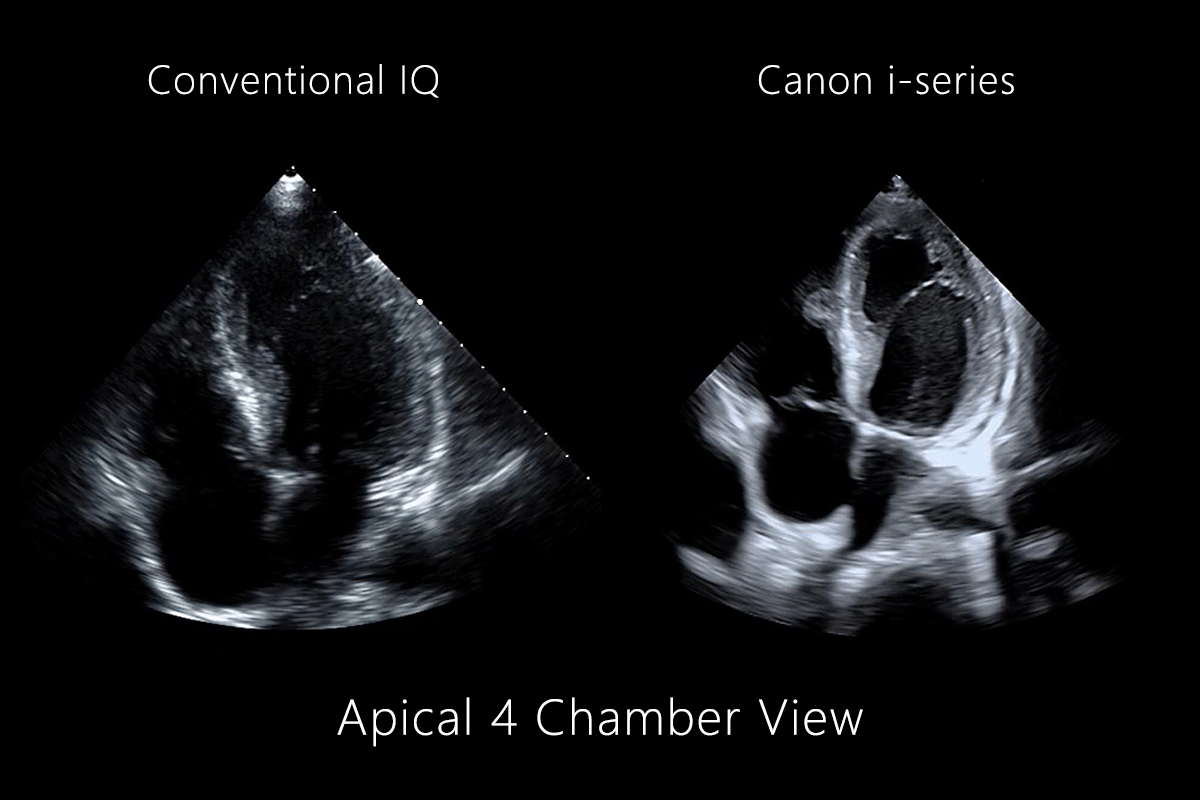

Image Quality for Difficult Patients

iBeam Forming